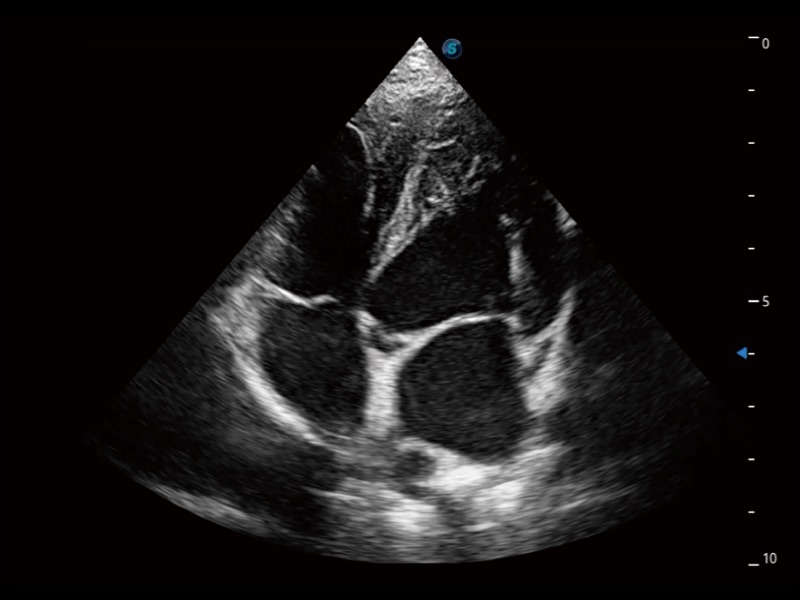

能够基于左心室壁追踪和辛普森法,自动计算射血分数,支持多个可移动点描迹,与手动测量相比,极大节省了动物医生的时间和精力。

通过360度任意调节3条M型取样线,在同一心动周期上观察心脏不同位置的运动曲线,得到准确的心功能测量数据,有效评估心肌运动及左心室功能。

实时用颜色表示心肌组织运动,观察和定量组织的运动情况,对快速检测与评估心肌的灌注和活性、电传导及心肌收缩和舒张功能等均能提供重要的诊断信息。

当心脏测量结果超出正常范围时,可实时预警提示动物医生,减少疾病漏诊概率。